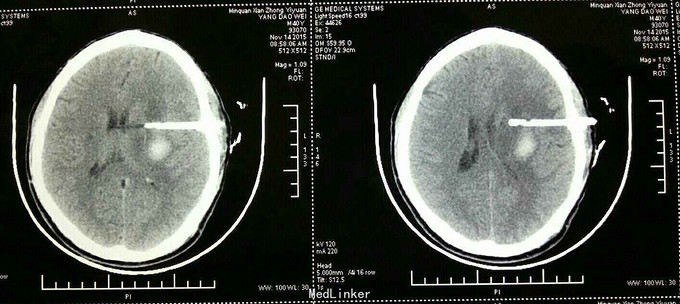

杨XX,男,40岁。 主诉:右侧上下肢无力伴失语15天。 病史:15天前在浙江务工时突然晕倒,随到浙江台州某医院就诊。神志清,精神差,查头颅CT示:“脑出血”,给予保守治疗。15天后家属要求转入原籍我院治疗。转入院时:神志清,精神可,血压:164/98mmHg,失语,右侧上下肢瘫痪,右侧上下肢肌力0级。 既往未检测血压。

诊断:高血压脑出血 治疗:微创钻孔血肿引流术。 术后应用尿激酶溶解血肿,引流顺利。 术后第四天拔除引流管。